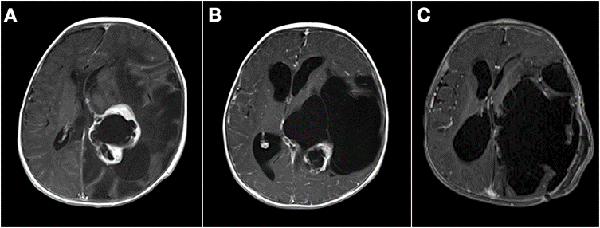

La resección parcial predominó en los grupos 1 (16 casos) y 2 (13 casos). De los 38 pacientes en los que se realizaron resecciones parciales 22 fueron lesiones supratentoriales, entre los cuales se encontraron 8 lesiones centro encefálicas (5 astrocitomas pilocíticos y pilomixoides, 1 craneofaringioma, 1 tumor embrionario indiferenciado y 1 hamartoma hipotalámico), 7 tumores de plexos coroideos (6 papilomas y 1 carcinoma de plexos coroideos) y 7 tumores hemisféricos. Por otro lado, 16 fueron lesiones infratentoriales (6 meduloblastomas, 3 teratoides rabdoides atípicos, 2 ependimomas anaplásicos, 3 astrocitomas pilocíticos, 1 pineoblastoma y 1 carcinoma de plexos coroideos). En la Figura 1 se muestran dos casos de abordajes a estos tumores.

Figura 1: Imágenes intra quirúrgicas de abordajes a tumores en SNC. A) Lesión sólido-quística cerebelosa hemisférica derecha, anatomía patológica: astrocitoma pilocítico. B) Lesión supratentorial intraventricular izquierda, anatomía patológica: papiloma de plexos coroideos.

Figura 2: A) Paciente de 3 meses de vida, sexo masculino, consultó por macrocefalia e irritabilidad, IRM de cerebro con contraste EV donde se evidenció lesión intraventricular izquierda con extenso edema cerebral ipsilateral. Se realizó cirugía con exéresis parcial debido a labilidad hemodinámica. Anatomía patológica informó papiloma de plexos coroideos. B) IRM de cerebro 1 mes postquirúrgica. Se decidió diferir la re-exploración. C) Se realizó nueva cirugía luego de 6 meses. IRM de cerebro 1 mes post quirúrgica donde se constató la exéresis completa. Paciente evolucionó favorablemente, recuperó pautas madurativas pérdidas.